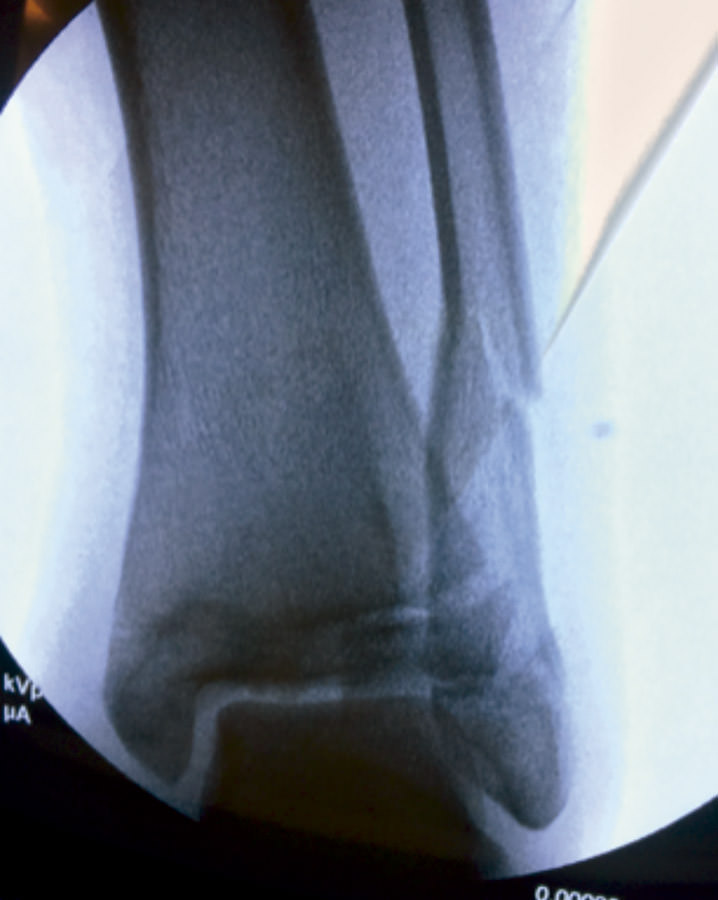

Bajo anestesia general se intentó la reducción cerrada de las fracturas, sin éxito (Figura 3).

Figura 3. Radiografía intraoperatoria después de reducción cerrada.